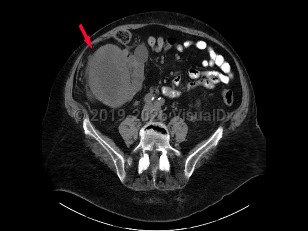

Renal cell carcinoma

Renal cell carcinoma (RCC) accounts for the majority of malignant neoplasms arising from the kidney. RCC is often asymptomatic until significant disease advancement, with 1 in 4 patients having advanced local disease or distant metastasis at presentation. Peak incidence is between the ages of 50 and 70 years, with a male-to-female ratio of 2:1. Risk factors for development of RCC include cigarette smoking, acquired cystic disease of the kidney, hypertension, obesity, occupational exposure (asbestos, cadmium, lead, petrochemicals), and von Hippel-Lindau syndrome.

Clinical presentation includes hematuria, abdominal pain, flank mass or abdominal mass, fever, weight loss, anemia, or varicocele. Many patients have tumors discovered incidentally with abdominal imaging performed for another reason.